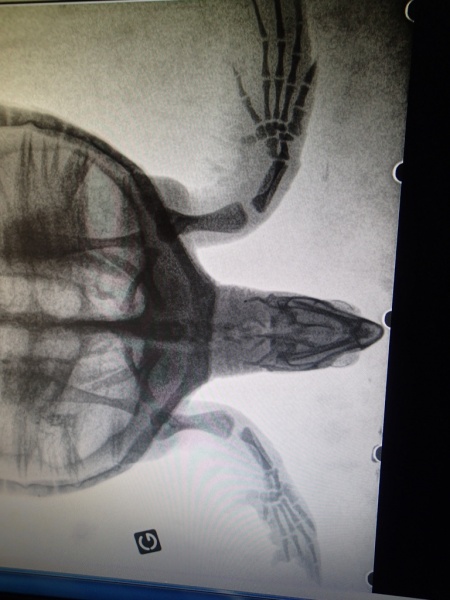

Visite chez le vétérinaire pour la jeune tortue imbriquée Adrien, annonce Kélonia. L'occultation des lésions confirme que la blessure date de plus d'une semaine. La cicatrisation a commencé. Un os de phalange qui restait attaché a été retiré. Et une radio de contrôle réalisée, qui n'a rien révélé d'anormal. Adrien a ensuite retrouvé son bassin sur le centre de soins. Les soigneurs réaliseront des soins locaux avec surveillance de l'évolution de la lésion jusqu'à cicatrisation complète. Et la tortue pourra retrouver le lagon dans quelques semaines, si tout se passe bien, explique Kélonia. (Photos Kélonia)